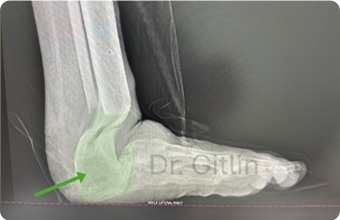

The picture below shows in the green color all of the new bone we created. Even though it will never look like the actual bones and joints it still functions to give the patient a usable limb. Under this X-ray you can see a picture of the patients foot after surgery. The patient is now over two years after surgery and can normally walk and run with his children.